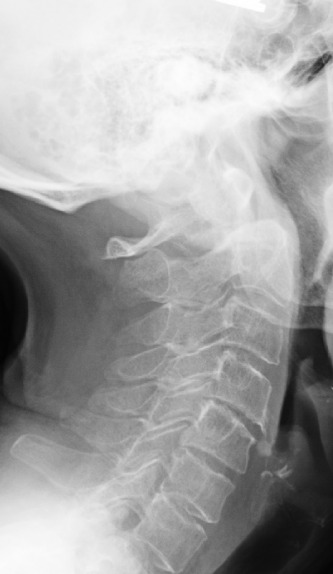

1. What is the key finding?

There are obvious degenerative changes of the cervical spine as well as osteopenia. The key finding however is the posterior subluxation of the atlas (C1) on the axis (C2). This is evident by the disruption of the spinolaminar line. The opacity with the sclerotic borders in the expected location of the dens represents the anterior arch of C1. Posterior to that you can make out the subtle appearance of a rounded opacity representing the dens, displaced posteriorly from the body of C2.

Diagnosis - Unstable Os Odontoideum

An os odontoideum may be confused with an acute fracture of the dens. An os may be differentiated from an acute fracture by its rounded sclerotic margins and wide gap between the bony fragments; a fracture will show a narrower gap with irregular non sclerotic margins.